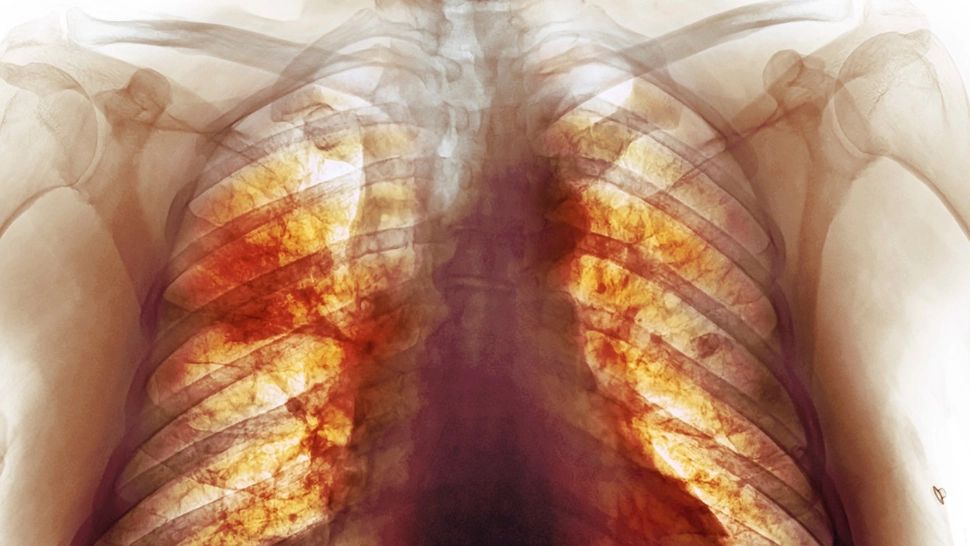

3 feb. 2022, 09:00ActualAdevărata dimensiune a dezastrului Covid. Cea mai detaliată radiografie dezvăluie cum arată, de fapt, plămânii după infectare - FOTO